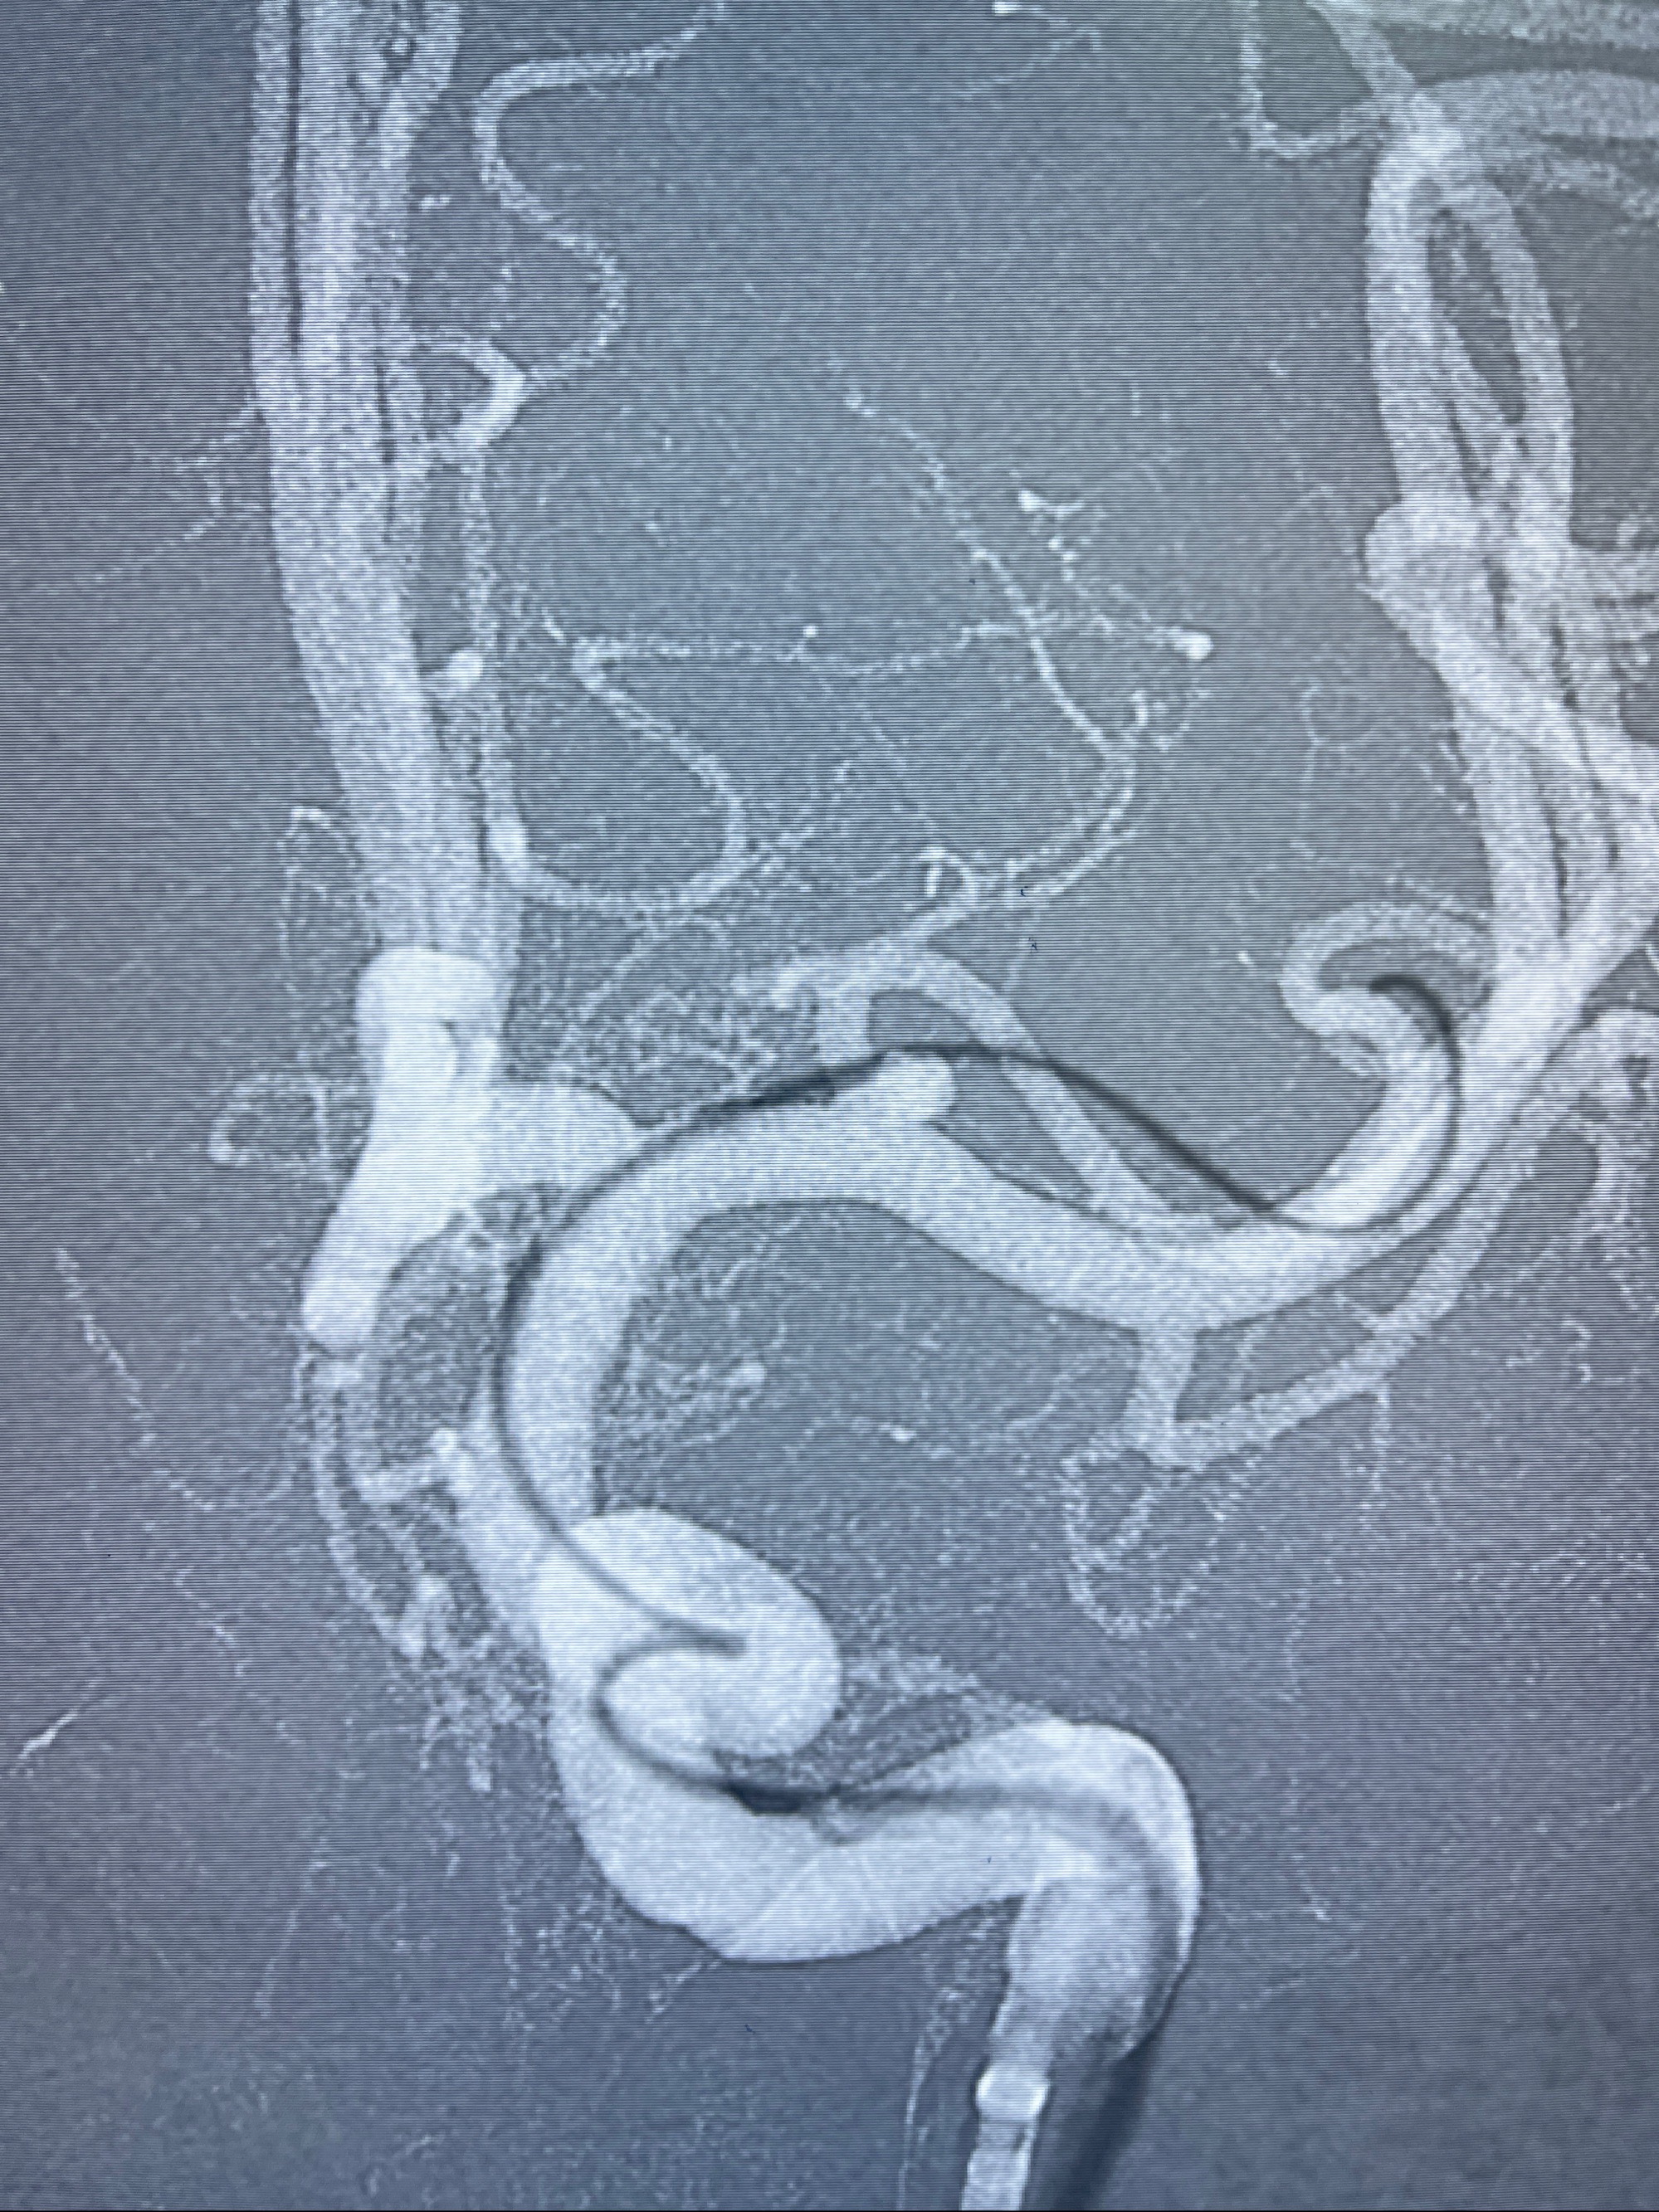

2023-08-14DSA:

左侧大脑中动脉动脉瘤,约2.6-2.8-3.4-2mm大小(瘤颈部、瘤体部、瘤高)